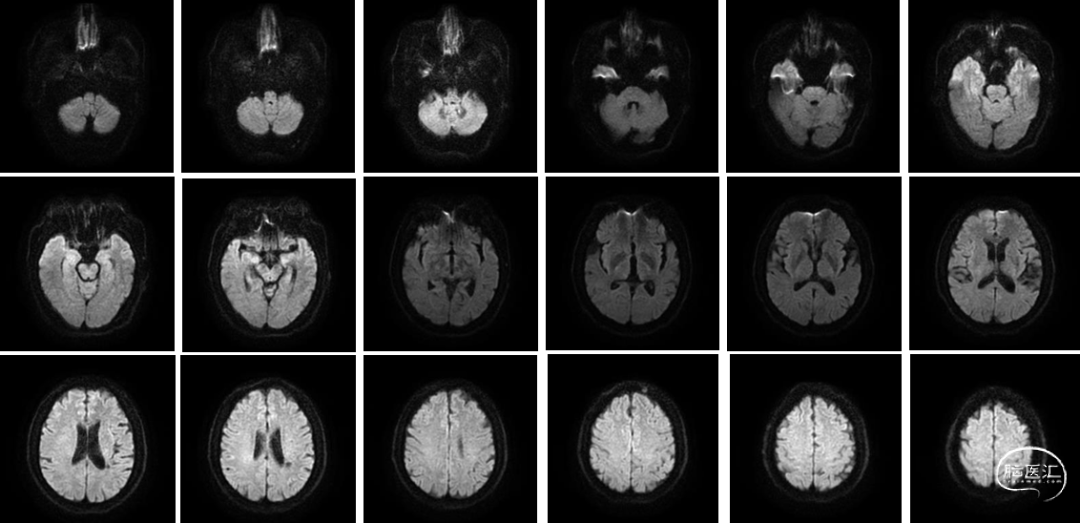

头颅MRI:未见新鲜脑梗死

DWI: